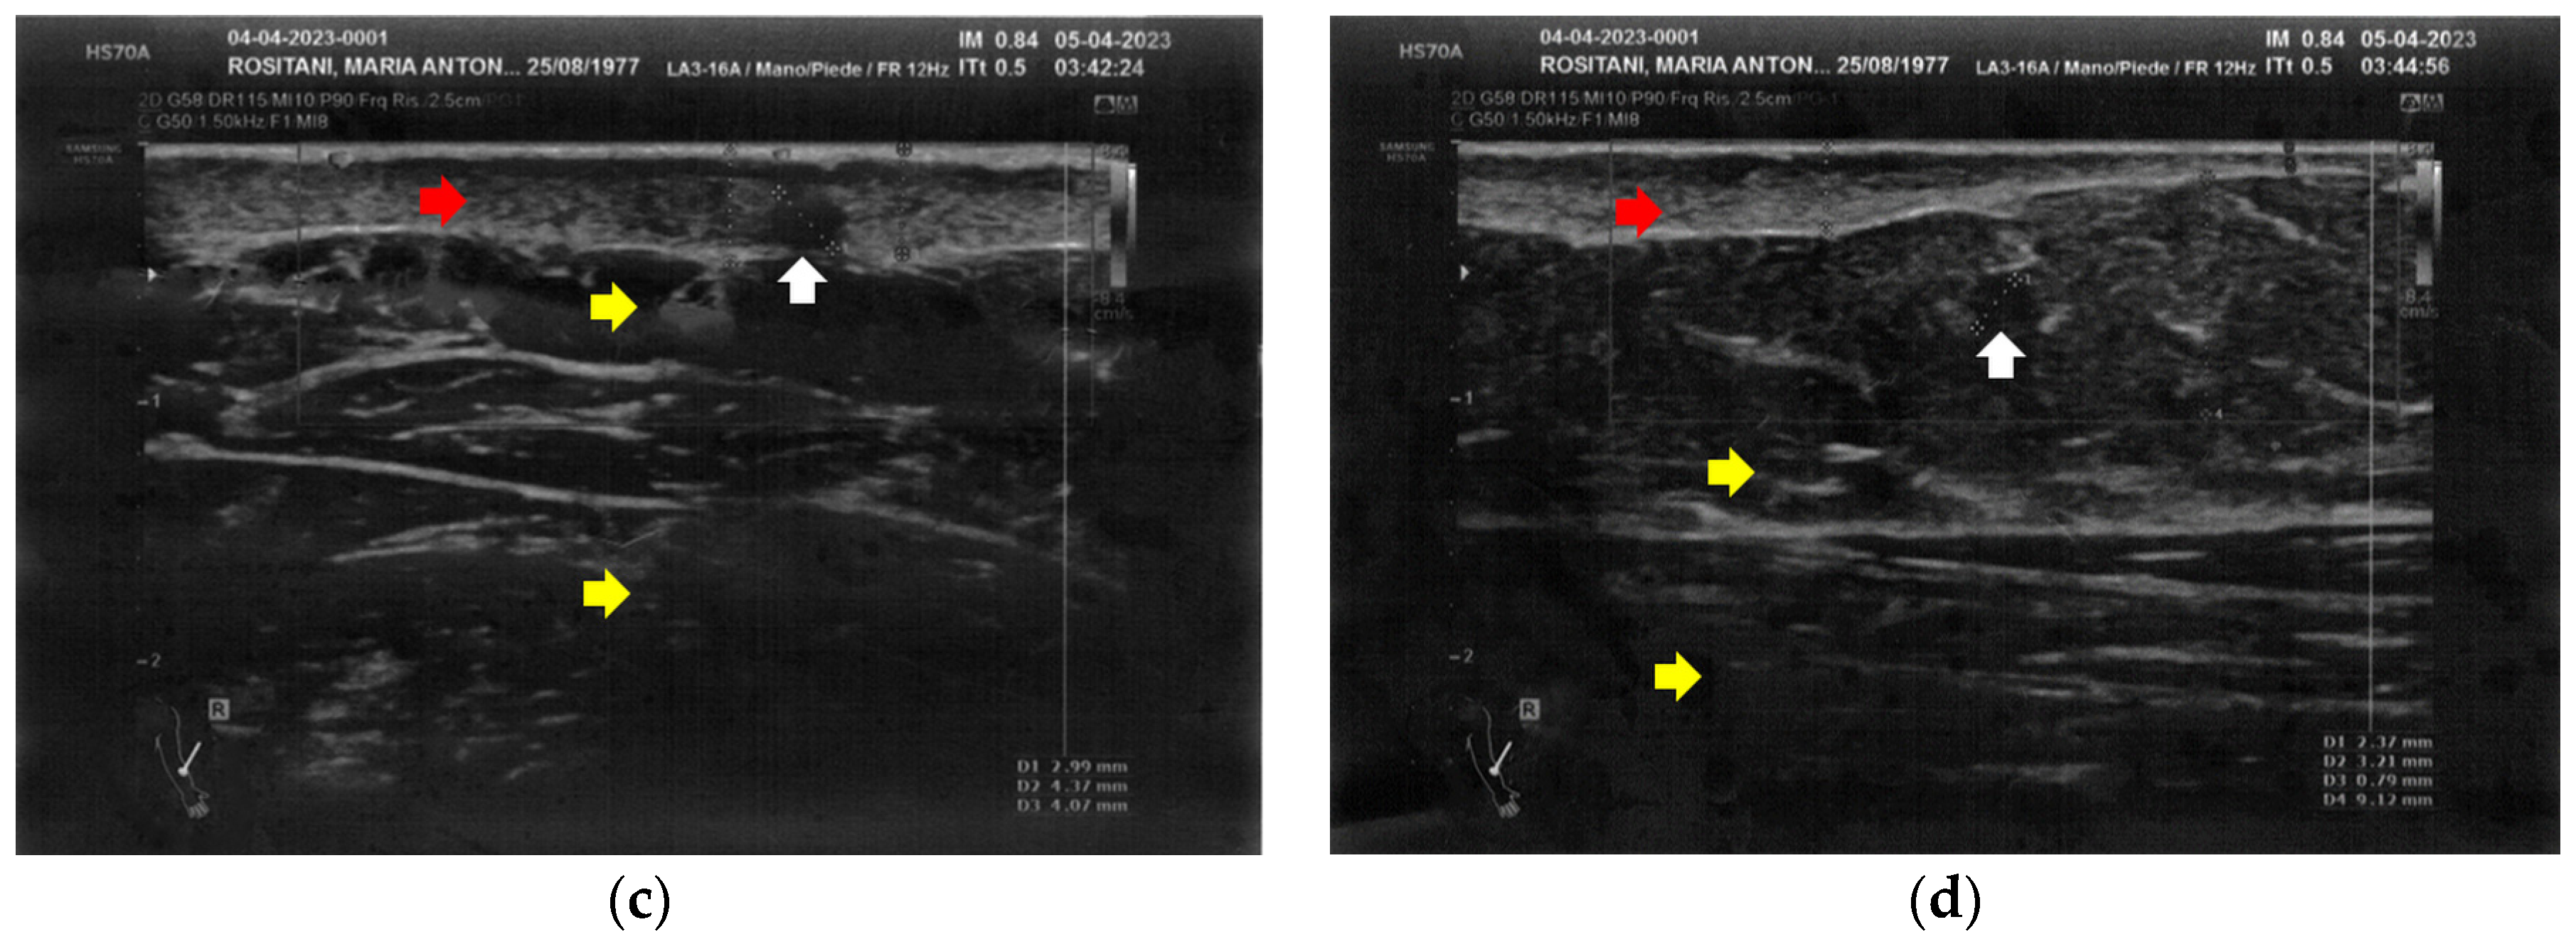

Similarly to the forearms, the popliteal fossae presented diffuse cicatricial fibrosis involving all the tissues down to the upper hypodermis layer. Even in these areas, cicatricial granulomas were present bilaterally, in correspondence to areas of previous abscesses, due to post-operative infections with rejection of the sutures and diastasis of the wounds. On the right side, some areas of minimal extension presented a partial inhomogeneous structural reorganization of the layers (Figure 3).

Figure 3.

Ultrasonography of the popliteal fossae at T0. (a) Wide section of cicatricial fibrosis (red arrow) of the left popliteal fossa with absence of clear anatomic layers (yellow arrow) and presence of a cicatricial granuloma (white arrow); (b) In another area of the left popliteal fossa the inhomogeneity of the tissues is evident (yellow arrow), and another cicatricial granuloma (white arrow) is present; (c) Cicatricial fibrosis (red arrow) is also evident on the right side, where the adipose tissue appears inhomogeneous (yellow arrows) and where multiple cicatricial granulomas (white arrow) are present in the deeper layer; (d) In another area of the right popliteal fossa, the superficial fibrosis (red arrows) appear less thick, and a partial restructuring of the deeper anatomical layers is noted (yellow arrow).